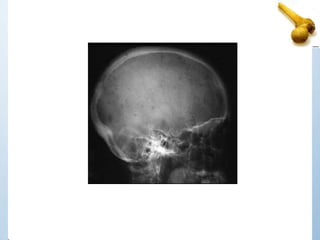

• Metastatic tumor most commonly attack the

skull, spine, pelvis, femur, humerus & often

involve more than one bone (polyostotic).